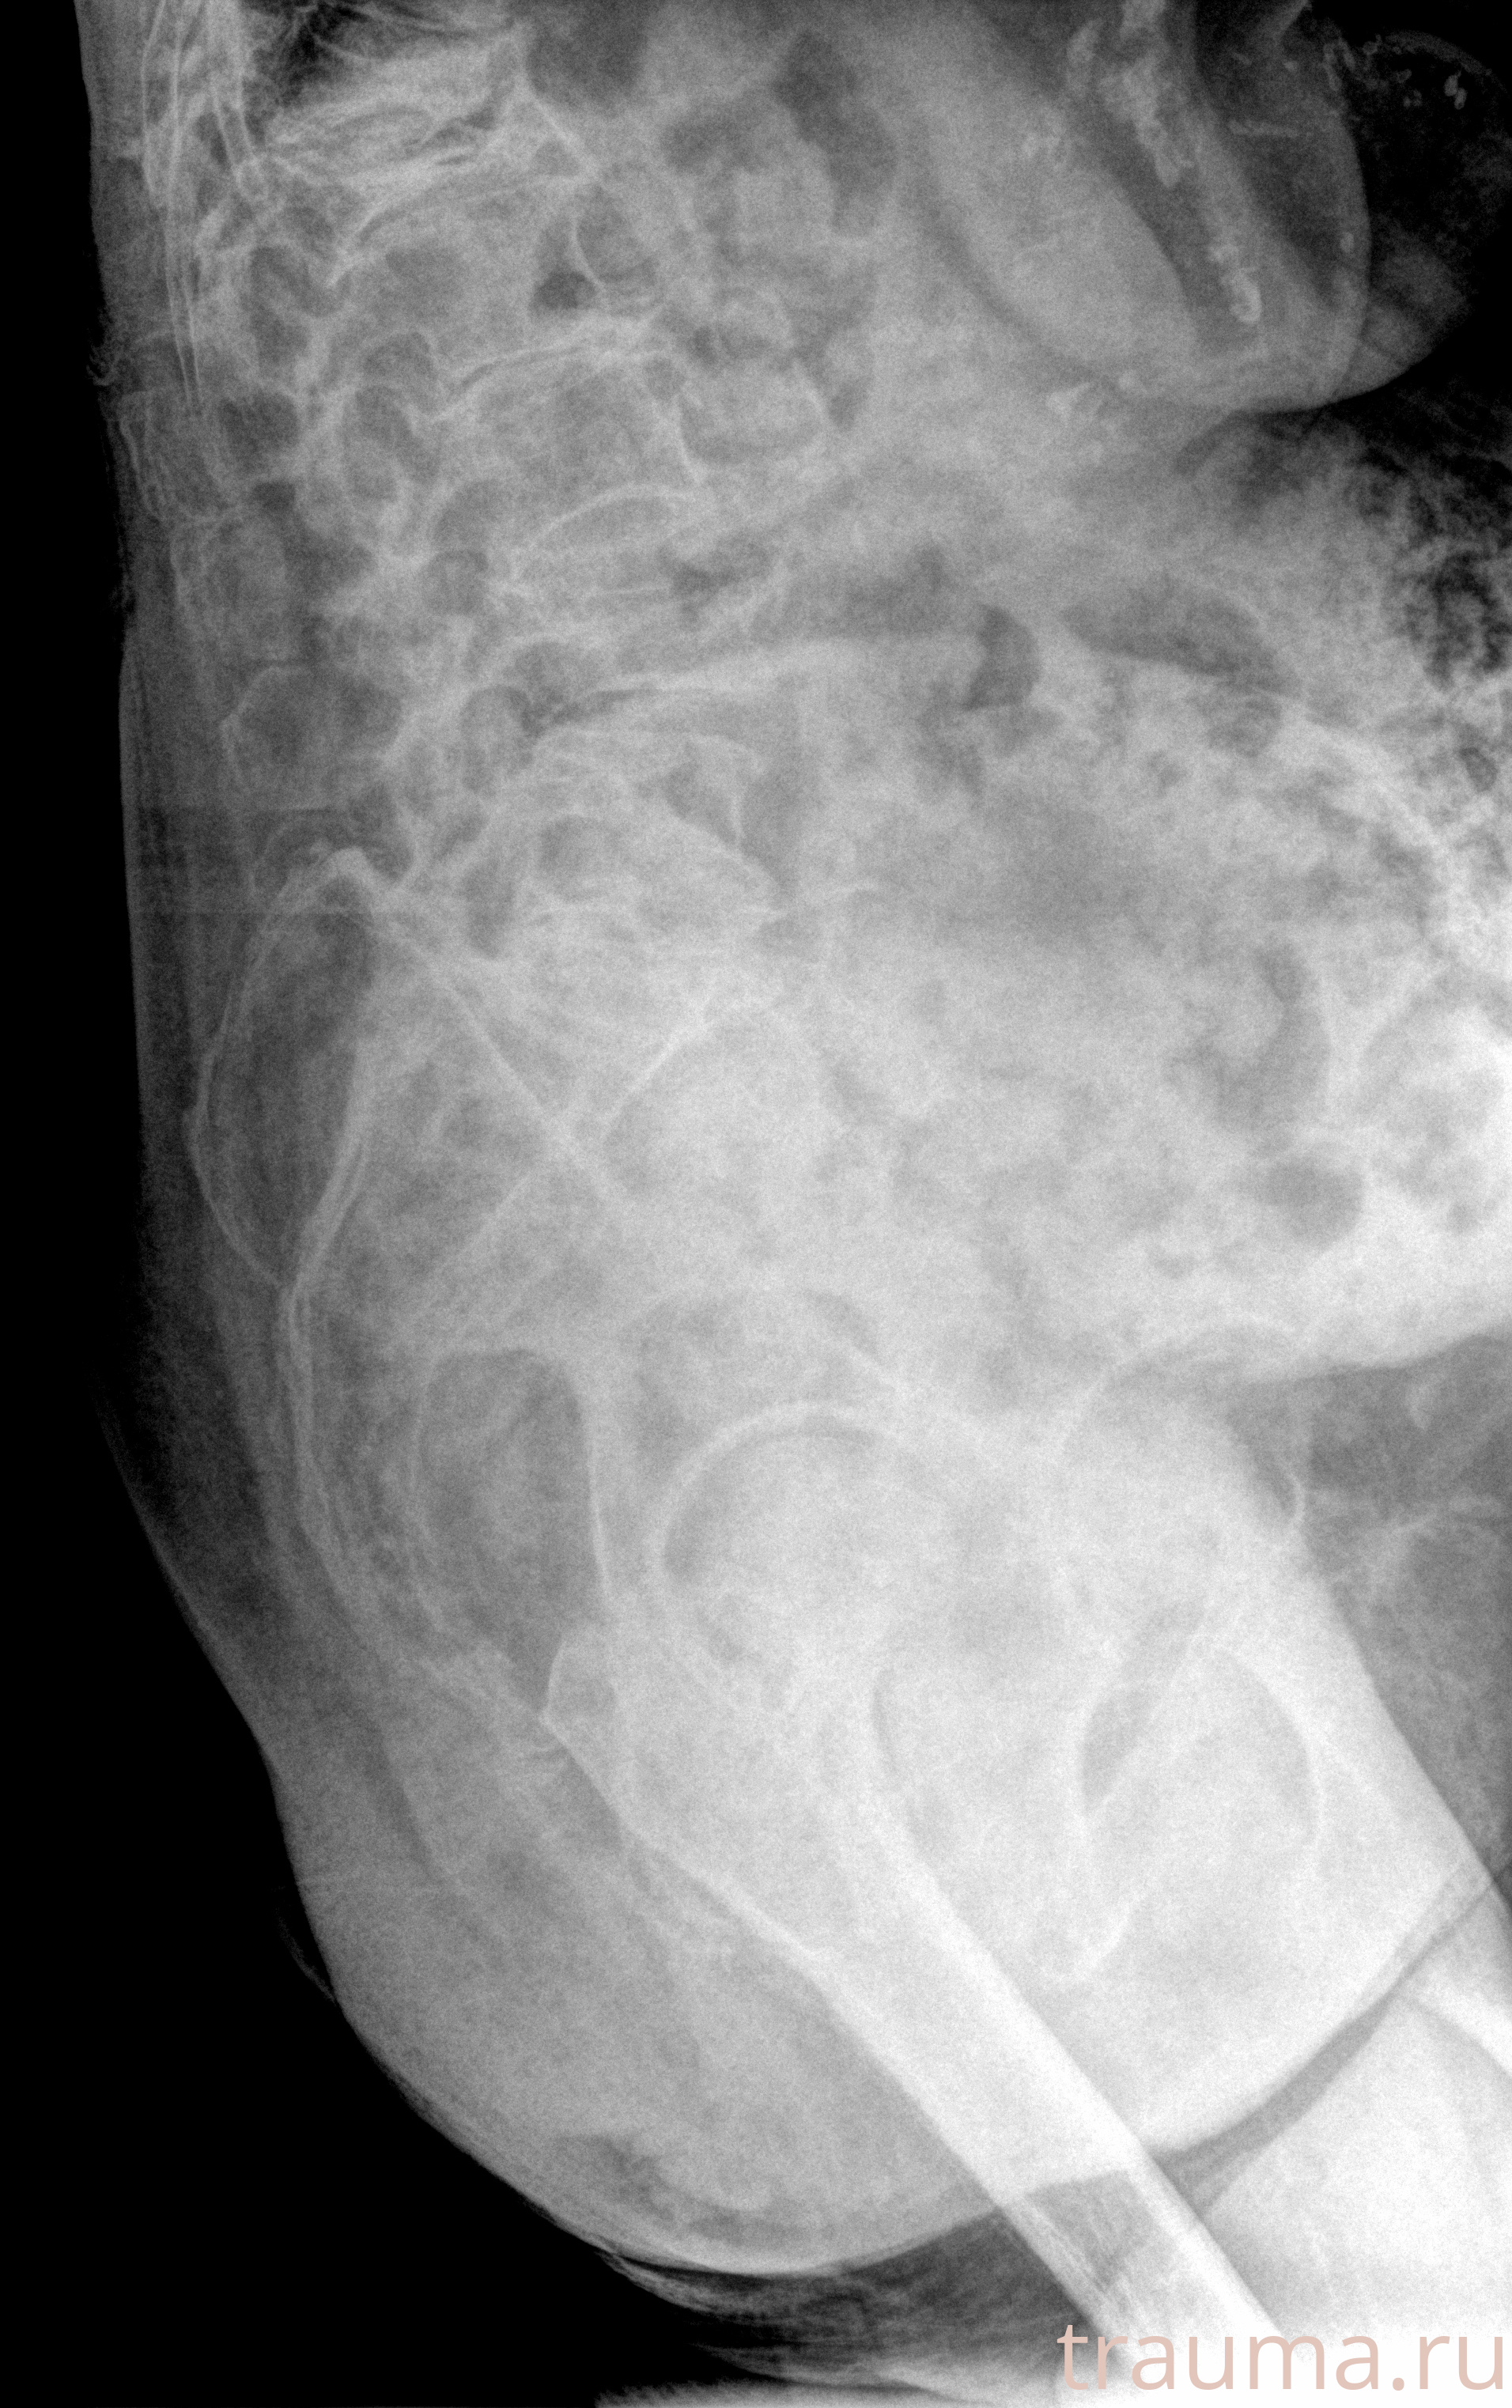

Рентгенограммы